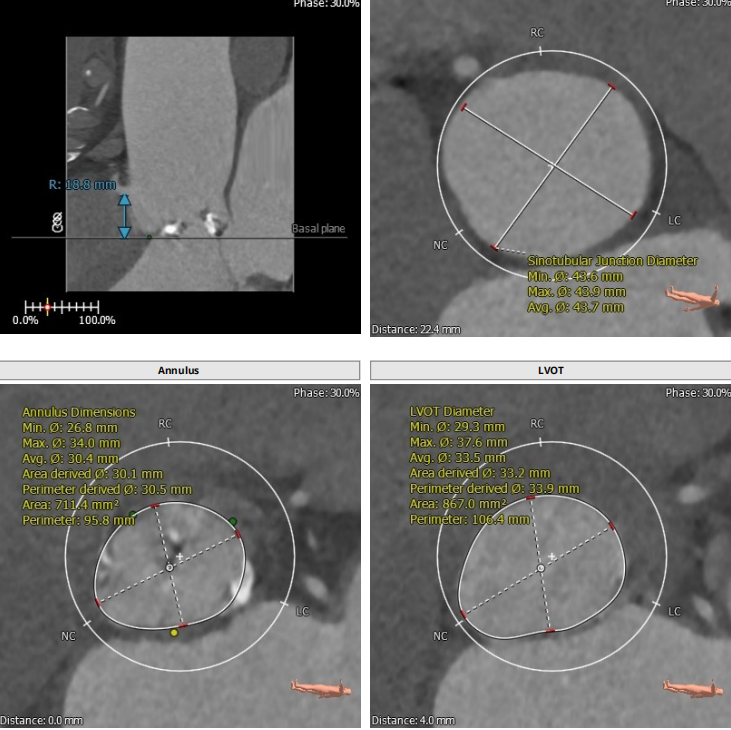

此例病人Type1二叶瓣,左右冠瓣融合,右无疑似融合,重度钙化,瓣环30.5,LVOT33.9,左右冠高度为16.9mm与18.8mm,右无融合离对侧28-30左右,STJ43.7,升主47.9,整体结构极大,心脏角度65度,近乎横位。